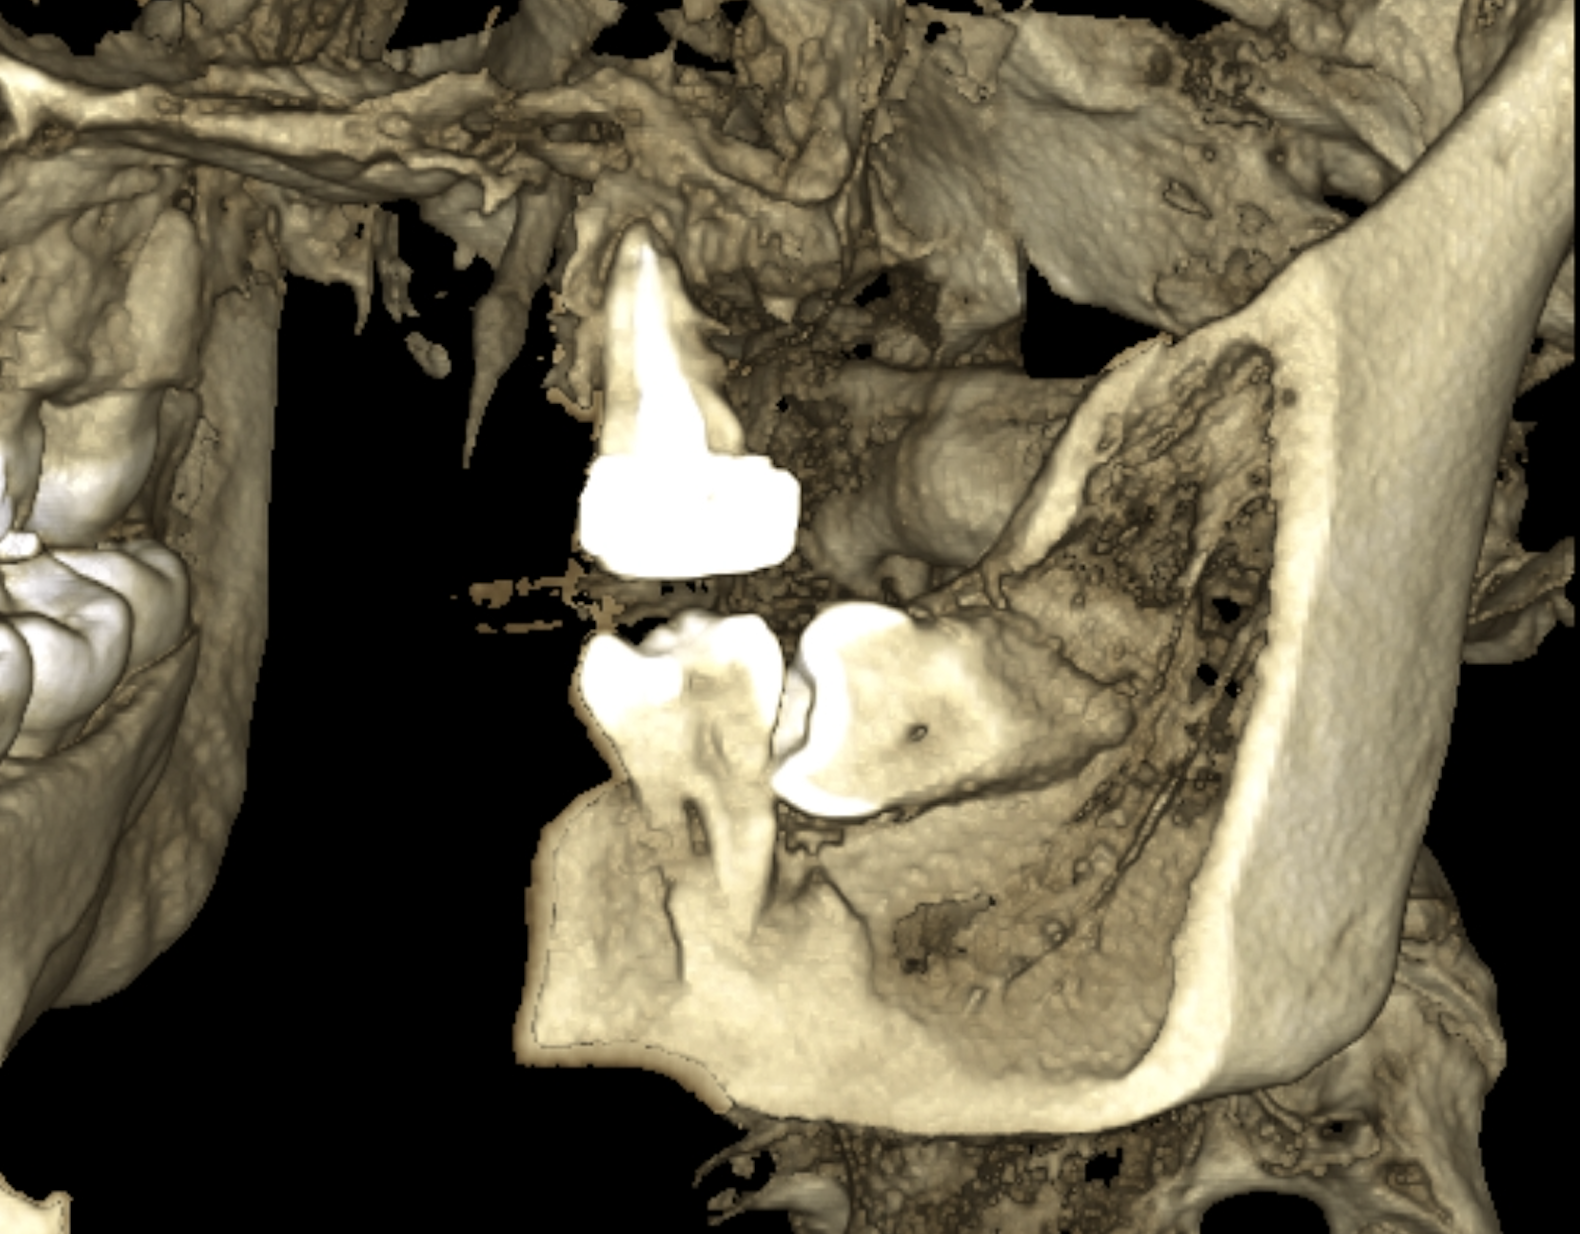

写真は同一部位のレントゲン写真とCT画像です。レントゲン写真は顎骨の形態や走行する神経の位置、歯が生えている方向把握することはできても2次元的な位置関係でしか把握できません。つまり歯や神経の位置がわかっていても実際にどのくらいの位置関係にあるのかを正確に判断することはレントゲン写真では不可能なわけです。しかし、歯科用CT画像では顎骨の形態や走行する神経の位置、歯の生えている方向、さらには骨密度の状態を3次元的に画像化する事が可能なため、より正確な診断する事ができます。